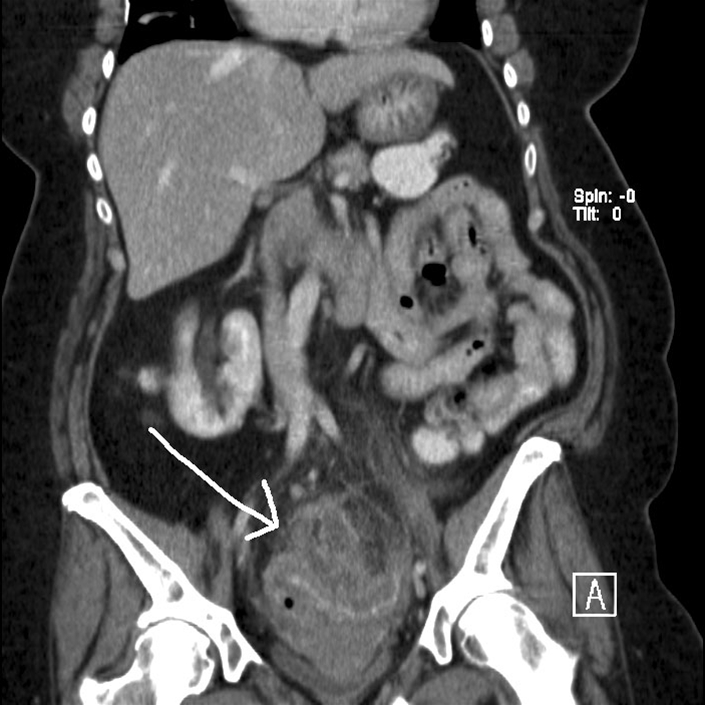

Diverticulitis i colon sigmoideum, længdesnit (CT)

CT scanning af abdomen hvor pilen peger på diverticulitis i colon sigmoideum.